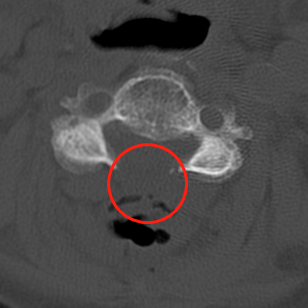

术前MRI影像提示胸椎黄韧带肥厚,胸段脊髓信号改变。

术前术后CT影像资料